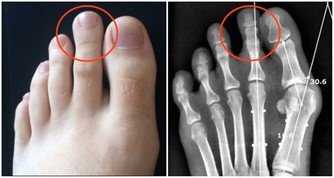

3、強直性脊柱炎

強直這種疾病是以腰痛為主要的首發症狀,但是腰痛的時候會伴隨著腰部變的僵硬的,尤其是早晨,腰部僵硬的需要活動很久才能好,這個在醫學術語裡面叫做晨僵,同時強直性脊柱炎患者會伴隨著脊柱的黏連,最後形成骨橋。

所以患者除了腰痛還會有活動受限的表現,比如患者自己伸直腿彎腰夠不著地,還比如呼吸不通暢,呼吸不通暢是因為影響了胸椎,才會出現呼吸不通暢的,再就是比較嚴重的患者會出現關節嚴重的變形,出現佝僂等表現。